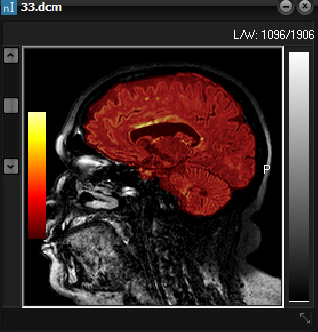

Screenshot

of original 3D volume (left) and resulting brain extracted volume (right)

after preforming a brain extraction session. The resulting extracted brain volume

overlaid on the original is shown below.